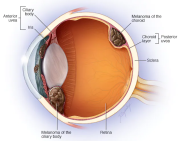

| 08:27, 30 באוקטובר 2023 | Eye melanoma2.jpg (קובץ) |  |

22 קילו־בייטים | Motyk | 1 | |

| 08:22, 30 באוקטובר 2023 | Eye melanoma1.png (קובץ) |  |

351 קילו־בייטים | Motyk | 1 | |